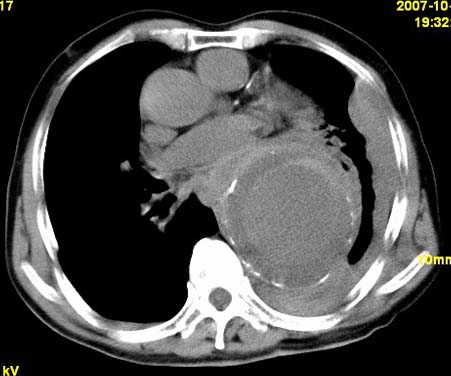

标题: CT10190:男,70,胸部疼痛数年,加重一天。典型病例。 [打印本页]

标题: CT10190:男,70,胸部疼痛数年,加重一天。典型病例。

典型降主动脉瘤伴血栓形成.瘤体下部局部边缘不清,结合病史,不除外局部撕裂外渗可能.另左侧胸水,肺部压迫不张改变.建议增强进一步检查.

典型降主动脉瘤伴血栓形成。支持:降主动脉瘤!

考虑胸主动脉瘤并血栓形成,胸腔积液

1.降主动脉瘤伴血栓形成.2.左侧胸腔积液,考虑为主动脉瘤破裂所致。

降主动脉明显增粗,边缘模糊,周围低密度影,双侧胸膜腔少量积液,结合临床考虑胸主动脉瘤破裂并双侧胸腔积液。